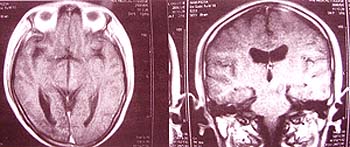

Trước đó bệnh nhân đã đến khám bệnh ở một số cơ sở y tế tại Hà Nội về lâm sàng, làm một số xét nghiệm cận lâm sàng và thực hiện một số kỹ thuật chẩn đoán cần thiết như chụp cắt lớp vi tính sọ não, chụp cộng hưởng từ sọ não. Kết quả cho thấy có khối u kích thước 30,2 x 20,4 mm, khối u choán chỗ vùng hạ đồi và não thất bên phía trái (không xác định được bản chất) chèn ép cống trung não, gây não úng thủy. Bệnh nhân được chuyển đến Trung tâm điều trị Phẩu thuật dao Gamma thuộc Bệnh viện Trường Đại học Y Dược Huế để điều trị.

Sau khi nhập viện, bệnh nhân được các bác sĩ ở Trung tâm Phẩu thuật dao Gamma và bác sĩ chuyên khoa ký sinh trùng hội chẩn. Nghiên cứu kỹ về yếu tố dịch tễ, các hình ảnh chụp cộng hưởng từ ở não, các dấu hiệu lâm sàng như lác mắt, song thị, liệt nhẹ nửa người bên phải ... Trong trường hợp này, ý kiến hội chẩn không loại trừ các bệnh ký sinh trùng hiếm gặp từ động vật nuôi lạc chủ sang người và đã cho bệnh nhân thực hiện một số xét nghiệm cần thiết như công thức máu, khám mắt, xét nghiệm ký sinh trùng ở phân, kỹ thuật Elisa huyết thanh để chẩn đoán ký sinh trùng, chụp cộng hưởng từ sọ não ... để có hướng chẩn đoán và điều trị. Kết quả ghi nhận trong công thức máu, bạch cầu lympho tăng 27%; khám mắt với thị lực mắt trái 5/10, 3/10 và mắt phải 8/10, 4/10; song thị khi nhìn sang trái. Đặc biệt với kỹ thuật Elisa huyết thanh chẩn đoán ký sinh trùng ghi nhận kết quả Toxocara canis (giun đũa chó) dương tính nồng độ 1/600. Chụp cộng hưởng từ sọ não cho thấy có khối u 1 x 1,5 x 1,5 cm ở thân não. Căn cứ vào các cơ sở dữ liệu đã thực hiện, hội chẩn thống nhất điều trị theo hướng nhiễm ký sinh trùng, không can thiệp điều trị hở bằng phẩu thuật, chưa có chỉ định điều trị bằng phẩu thuật dao Gamma.

Khối u não thật trước khi điều trị (trên) và sau khi điều trị (dưới) |

Sau khi điều trị 2 đợt theo quy trình quy định, khám lại bệnh ghi nhận thể trạng bệnh nhân tốt, ăn ngủ bình thường, hết nhức đầu, nhìn rõ, hết song thị, mi mắt trái còn sụp nhẹ. Khám mắt với thị thực mắt trái 10/10, mắt phải 10/10; vận động mi mắt, nhãn cầu tốt; thị trường đối chiếu không phát hiện tổn thương; soi đáy mắt thấy gai thị, mạch máu, võng mạc bình thường. Bệnh nhân có vận động hoàn toàn bình thường, không có dấu hiệu bị liệt. Đặc biệt chụp cộng hưởng từ sọ não ghi nhận khối u ở thân và cuống não trái đã thoái triển nhiều, giảm kích thước so với trước từ 1 x 1,5 x 1,5 cm còn lại 1 x 0,5 x 1 cm; dấu hiệu phù não quanh khối u và hiệu ứng choán chỗ giảm đáng kể; không thấy bất thường mới ở các thùy não khác, tiền não, màng não; thương tổn trước đây ở thân cầu não trái giảm rõ rệt. Hiện nay, bệnh nhân ăn uống, sinh hoạt, lao động và học tập trở lại bình thường.